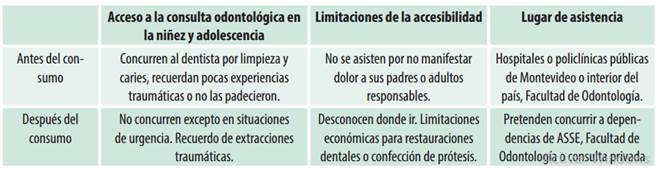

En relación a la accesibilidad a la atención odontológica se reconocen diferencias antes y después de la adicción a SPA (cuadro 5).

La accesibilidad a la consulta odontológica se realizaba en forma regular y criterio preventivo, eventualmente curativo, de preferencia en dependencias públicas o en la Facultad de Odontología, en épocas previas al consumo. Una vez generada la situación de dependencia a SPA, la atención pasó a ser esporádica en casos de urgencia, con terapias sedantes o quirúrgicas, muchas veces traumáticas para el paciente. Relatan deseos de mejorar su estado bucal aunque los costos y la escasez de recursos se lo impiden.